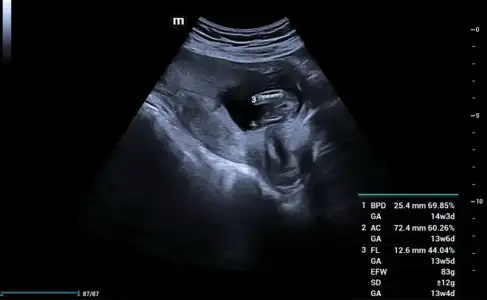

13+4 tahminde bulunabilir misiniz şimdiden teşekkür ederim.

Eklentiler

• AB07C4B8-4141-4E2D-B914-B8AE22ADA7A7.webp

AB07C4B8-4141-4E2D-B914-B8AE22ADA7A7.webp

22,2 KB · Görüntüleme: 70